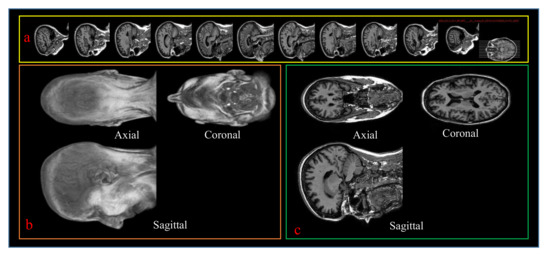

4.1. Dataset